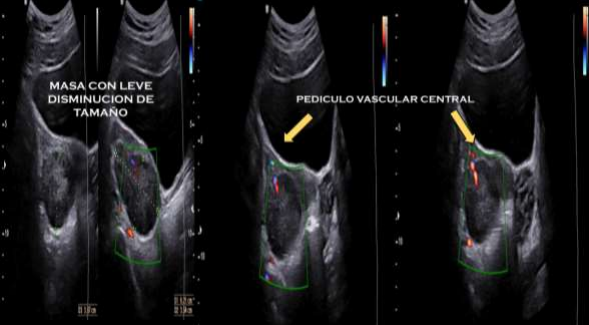

Eight days after surgery, an ultrasound control was performed, finding an adnexa that remained enlarged, however, with a central irrigation pedicle. (Fig. 3)

Figure. 3. Ultrasound control with central ovarian pedicle.